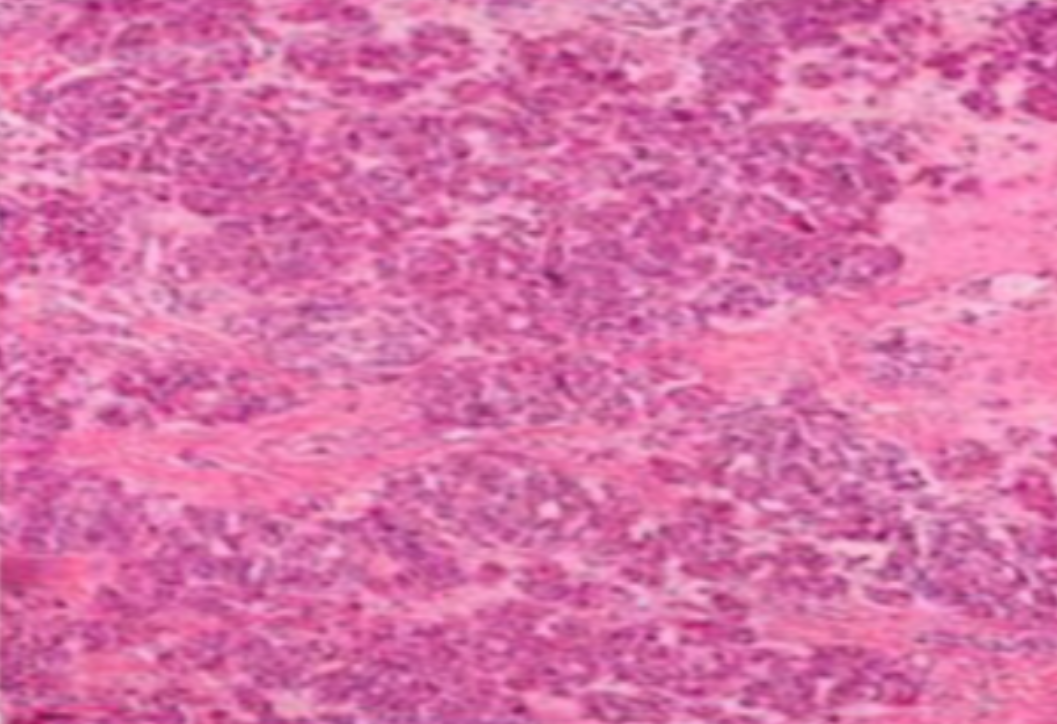

HE染色,全称苏木精-伊红染色法(Hematoxylin and Eosin staining),是最常见的组织切片染色技术之一,用于在显微镜下观察和分析组织或细胞的结构和形态。

虽然HE染色是最常见且最基础的染色技术之一,😭但在实验过程中,很容易出现各种情况导致染色切片质量参差不齐。所以,小编根据以往实验经验,给大家整理归纳出了15个HE染色中的常见问题,还包含问题原因分析以及解决方法哦~

形成原因:切片经梯度乙醇处理后没有完全脱水,导致二甲苯透明、中性树胶封固后残留大量水分。 解决方法:首先移去盖玻片,用二甲苯溶解封固剂如中性树胶,再将切片置入无水乙醇内,待切片重新脱水完全后,用二甲苯透明处理,中性树胶封固。要注意所有用于脱水和透明的液体,在使用一定时间后,应及时更换。 二、细胞核呈红、棕色 形成原因:苏木精染色液过度氧化,切片在苏木精染液染色后返蓝不足。 解决方法:每次染色之前检查苏木精染色液的染色能力,发现苏木精染色液氧化过度应及时更换。此外,切片经苏木精染色后,要给切片以足够的蓝化时间,蓝化过程可用流水、温水、弱碱性溶液(如稀氨水或0.2%碳酸氢钠)等处理。 三、切片在脱蜡后出现大片白色斑点 形成原因:由于烤(烘)片温度太低,切片上的组织蜡膜在脱蜡前没有充分烤(烘)融化。或是因为切片在二甲苯液中停留时间不足,或二甲苯使用过久,造成的脱蜡不彻底。 解决方法:若是由于切片烤(烘)温度低所致,可以先用二甲苯去除切片上的封固胶,然后重新用二甲苯脱去切片上的石蜡,再进行后续染色。若是由于切片在脱蜡的二甲苯中停留时间不足或脱蜡二甲苯使用过久浓度不足所致,则需将切片退回到二甲苯中,停留较长时间,或更换二甲苯液体重新脱蜡,再入乙醇重新脱二甲苯,入0.5%盐酸水溶液褪色后,重新HE染色。 四、细胞核苍白暗淡,即苏木精染色太淡 形成原因:切片在苏木精染色液停留时间太短;苏木精染色液过度氧化,失去染色能力,不能再继续使用;分化步骤处理时间过长;固定不及时。此外值得注意的是,若骨组织细胞核暗淡,大多是脱钙过度造成的。 解决方法:切片重新染色。如果组织在酸性固定液(如Zenker、Bouin)或非中性缓冲甲醛液固定时间过长,细胞核染色能力将减弱,需增加其在苏木精染色液的时间,或用一些方法增加组织的嗜碱性,以改善细胞核的着色。例如,上述组织玻片可以使用Weigert铁苏木精染色液。如果组织是用Zenker液固定的,可将切片脱蜡后放在5%碳酸氢钠溶液3~4h,流水冲洗5min后染色。如果组织是用Bouin液固定的,可将切片脱蜡后放在5%碳酸锂1h,流水冲洗10min后染色。 五、细胞核过染,苏木精染液占据了细胞质 形成原因:玻片在苏木精染色液停留时间过长,或是切片太厚、分化步骤时间太短。 解决方法:如果不是因为切片太厚(用显微镜仔细上下微调,只有一二层细胞核层次),就需将切片进行脱色、漂白、重新染色,适当调整染色和分化时间。但如果确定是由于切片太厚导致的细胞核过染,则需要重新切片。 六、伊红着色淡 形成原因:可能是伊红染液pH值大于5,也可能是蓝化液残留过多,切片太薄,或是切片经伊红染色后在乙醇脱水时间过长。 解决方法:检查伊红染液pH值,必要的话,用乙酸将其调节在4.6~5.0之间,从而使伊红染色色彩艳丽。此外,确保每次蓝化步骤完成后,使用的弱碱性溶液被充分洗去,玻片上没有残留的弱碱性溶液。最后,检查切片的厚度,且脱水时不要让切片在低浓度乙醇中停留时间过长,因为含水多的低浓度乙醇会将切片伊红的颜色分化掉。 七、细胞质过染、分色不足 形成原因:伊红染色液浓度太高,特别是存在焰红燃料、四溴四氯荧光素钠。切片在伊红染色时间过长,或是切片在伊红染色后经乙醇脱水步骤时时间太短,而使乙醇分化伊红的作用不能产生,都能够使细胞质过染。 解决方法:适当稀释伊红染色液,减少伊红染色时间,或使切片在乙醇脱水等步骤时,停留时间相对均匀。同样,也要检查切片的厚度是否合适。 八、切片中出现蓝黑色沉淀物 形成原因:苏木精染色液中的金属膜黏附在玻片上。 解决方法:染色前仔细过滤苏木精染色液,建议使用半氧化苏木精染色液,如Gill苏木精染色液,可以避免过多的金属膜产生。 九、光镜下切片某些区域难以聚焦 形成原因:盖玻片上可能有封固切片的封固剂。 解决方法:移去盖玻片,重新用干净的盖玻片封片。检查切片封片方法,是人工手工封法,还是机器自动封法,如有问题及时调整。 十、封固剂从盖玻片与载玻片之间的缝隙回缩 形成原因:盖玻片弯曲或不平整,或是封固剂含二甲苯过多,稀释过度。 解决方法:移去盖玻片,重新找一张盖玻片,用干净的封固剂封片。如用手工封片法,保证在封固结束时,封固剂容器盖子为紧闭状态。且尽量使用小的容器盛装封固剂,一旦封固剂太黏稠,就可以选择废弃。 十一、细胞核呈灰蓝状态 形成原因:可能由于组织处理温度过高、过热,在液体石蜡中停留的时间过长。或是固定时间太短后,直接在高浓度的乙醇中进行了脱水处理。 解决方法:理论上来说,仅在组织浸蜡步骤才进行加热,组织不能在热蜡液中停留太久。如果由于某些原因不能进行下一步包埋处理,可将组织连同塑料包埋盒一并放置在室温空气中,冷却凝固,以备包埋。待需要包埋时再重新加温直至石蜡融化即可。组织在处理前必须确保固定良好,脱水最好能从低浓度的乙醇开始。 十二、类色素的点状结晶和黑色光滑细胞核 形成原因:这种裸核改变是因为切片封片前放置在空气中的时间太长,以至于二甲苯挥发,切片干燥。 解决方法:移去组织切片上的盖玻片和封固剂,重新处理。将切片水洗数分钟,然后重新脱水、透明、封固。封片过程中要保持组织切片的轻度湿润,尽量不要让其干燥。 十三、染色过淡或过浓 解决方法:如果染色过淡,可以增加染色剂的浓度、延长染色时间或更换新鲜的染色剂;如果染色过浓,则应减少染色剂的浓度或缩短染色时间。 十四、切片出现叠加褶皱 形成原因:新购买的玻片洁净度不够、用镊子撑开切片时操作不够熟练未能平整伸展,或玻片表面有油脂,切片粘贴不牢。另外,烤片时间不足、烤片温度过低或切片过厚造成切片脱落,都会造成重叠或有皱褶的情况。 解决方法:新购买的玻片最好能用硫酸清洁液浸泡一晚,然后流水冲洗干净。在适宜的温度下烤片时间宁长勿短,保证有充足的烤片时间和温度。另外,切片刀要锋利,才能切出厚薄适宜的切片,保证切片不会因为过厚而脱落。 十五、组织残缺不全或有刮划痕迹 形成原因:组织残缺不全是由于切片时修整蜡块时深度不够、组织没有全部暴露于切面。切片的刮划痕迹是由于切片刀的刀锋有缺口、包埋的组织有异物,或是钙化组织、骨组织及包埋石蜡有沙粒造成的。 解决方法:修整蜡块时保证组织块全部暴露于切面,切片时保证切片刀的锋利没刀口。同时在组织取材时去除手术异物和钙化组织。最后,骨组织要完全脱钙,这样可以保证切片的完整和平整美观。 *注:由于实验中导致结果出现误差的原因多种多样,以上内容仅供参考,具体根据实际情况进行判断。